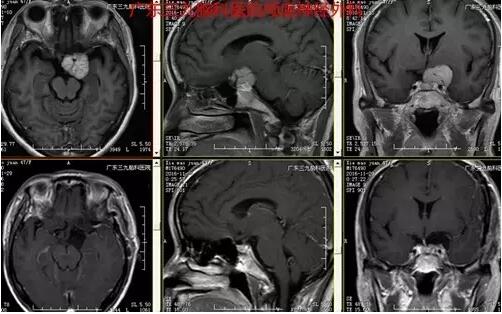

图3:术前MR提示左侧海绵窦区一团块状稍长T1稍长T2异常信号影,范围约2.8cm×2.8cm×2.3cm,增强后呈欠均匀明显强化,左侧颈内动脉终末段受包绕

图4:术前术后MR对比提示肿瘤全切除